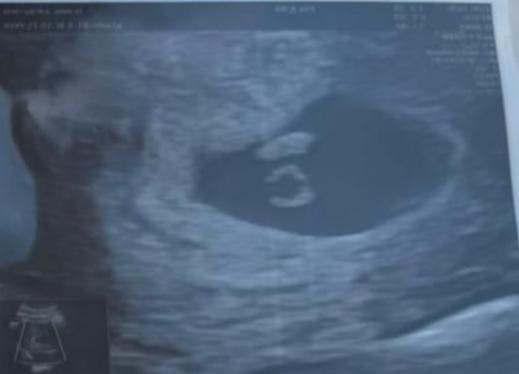

Мой бесценный бриллиант ❤️🩹

СубханАллаh, в эмбрионе размером 5,5 мм бьется сердце. Уму непостижимо.